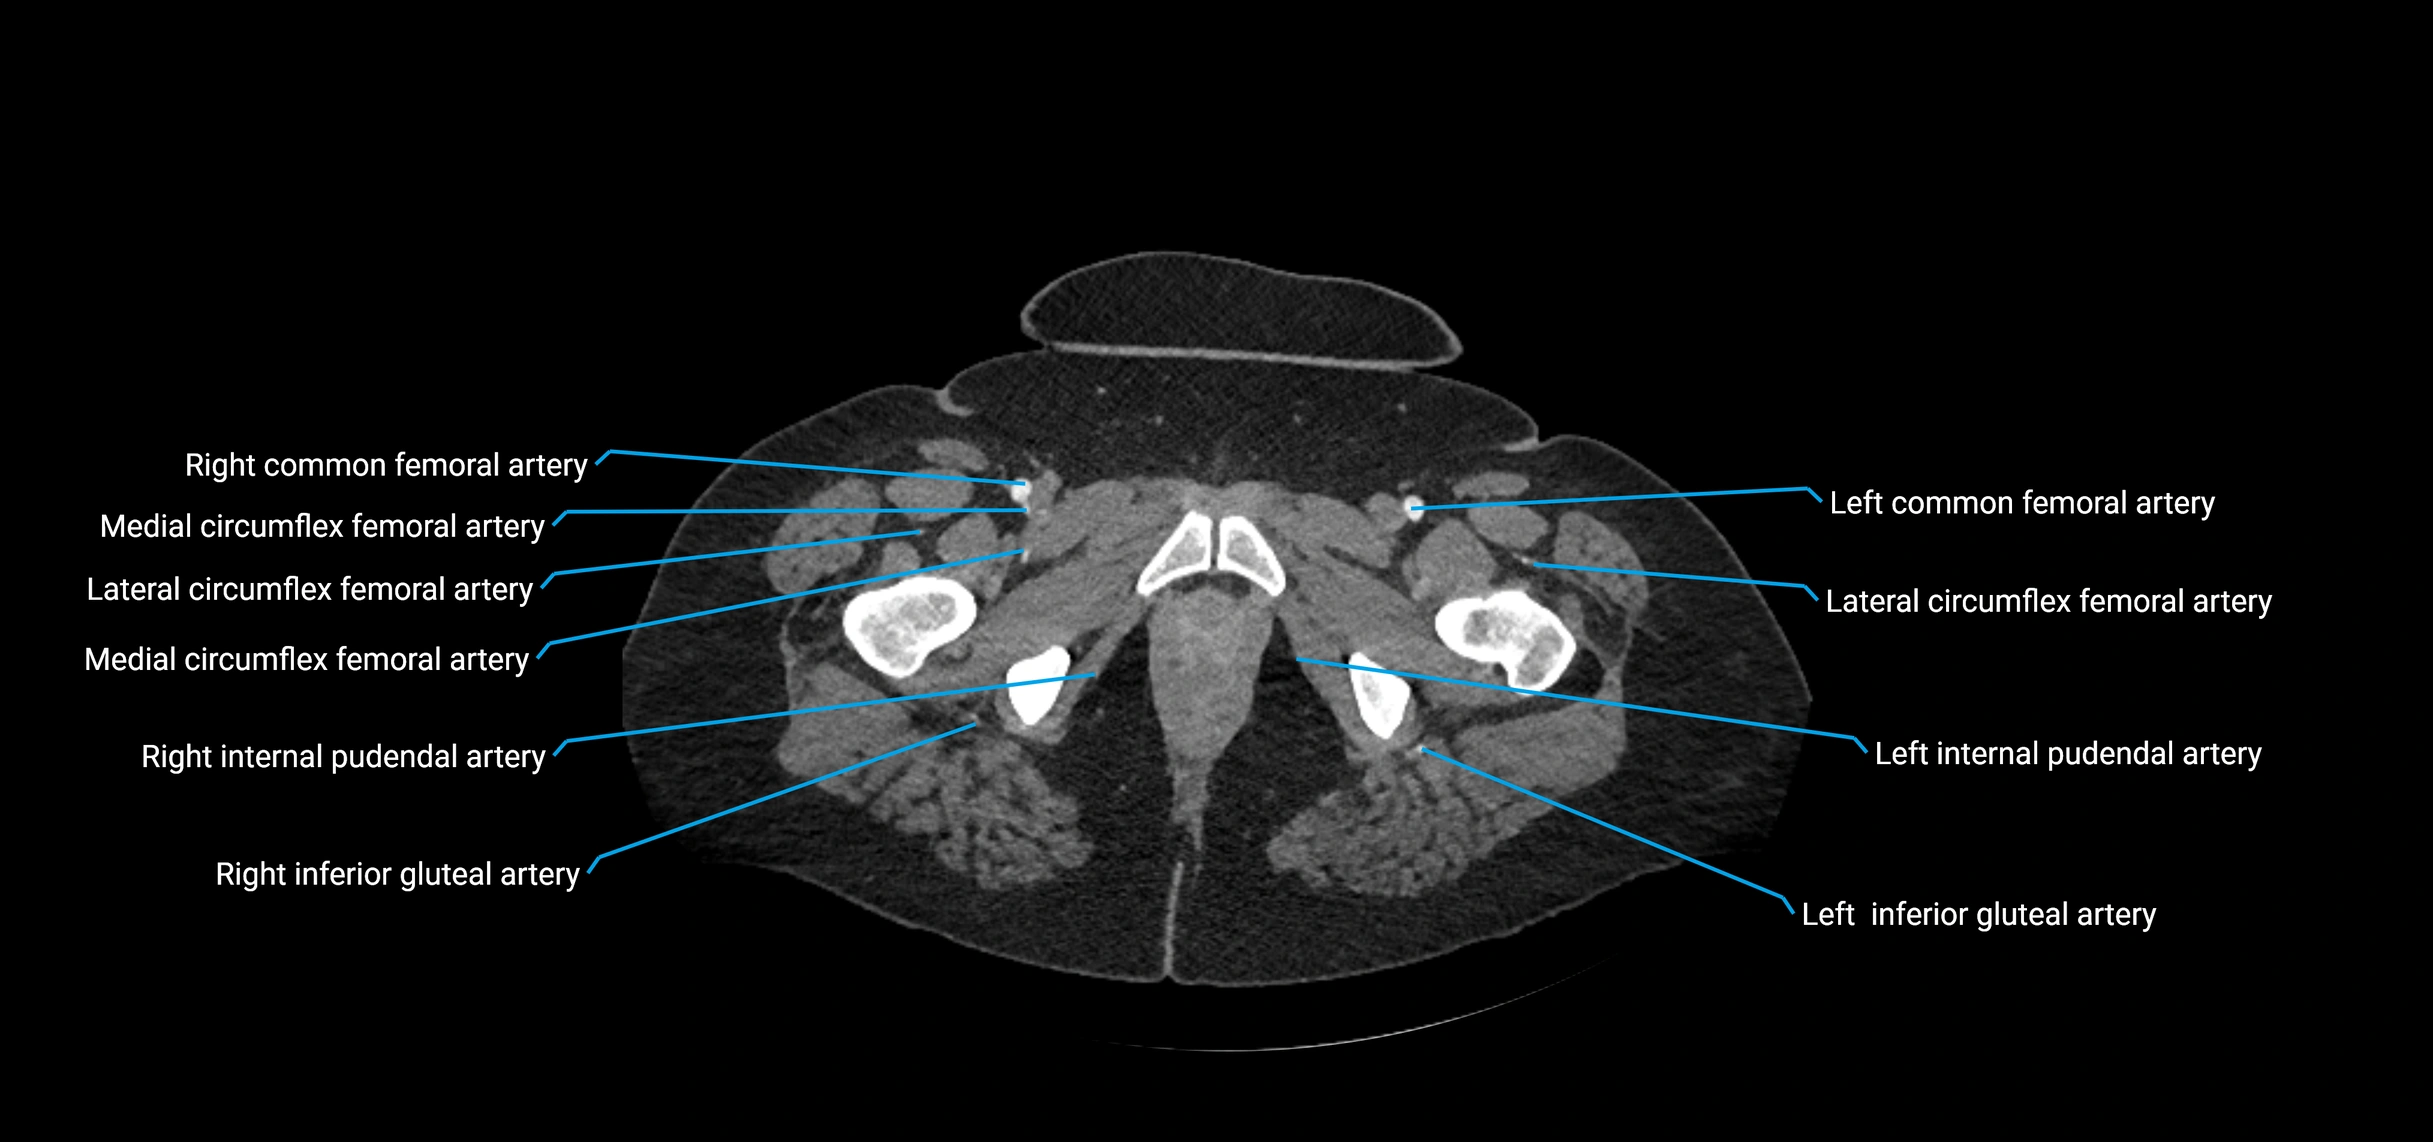

Contrast-enhanced CT (CTA):

• Gold standard for abdominal aortic imaging

• Provides excellent detail of lumen, wall, aneurysm, thrombus, and branch vessels

• Multiplanar and 3D reconstructions help in aneurysm measurement, stent graft planning, and dissection evaluation

• Detects acute rupture, traumatic injury, or occlusion with high sensitivity